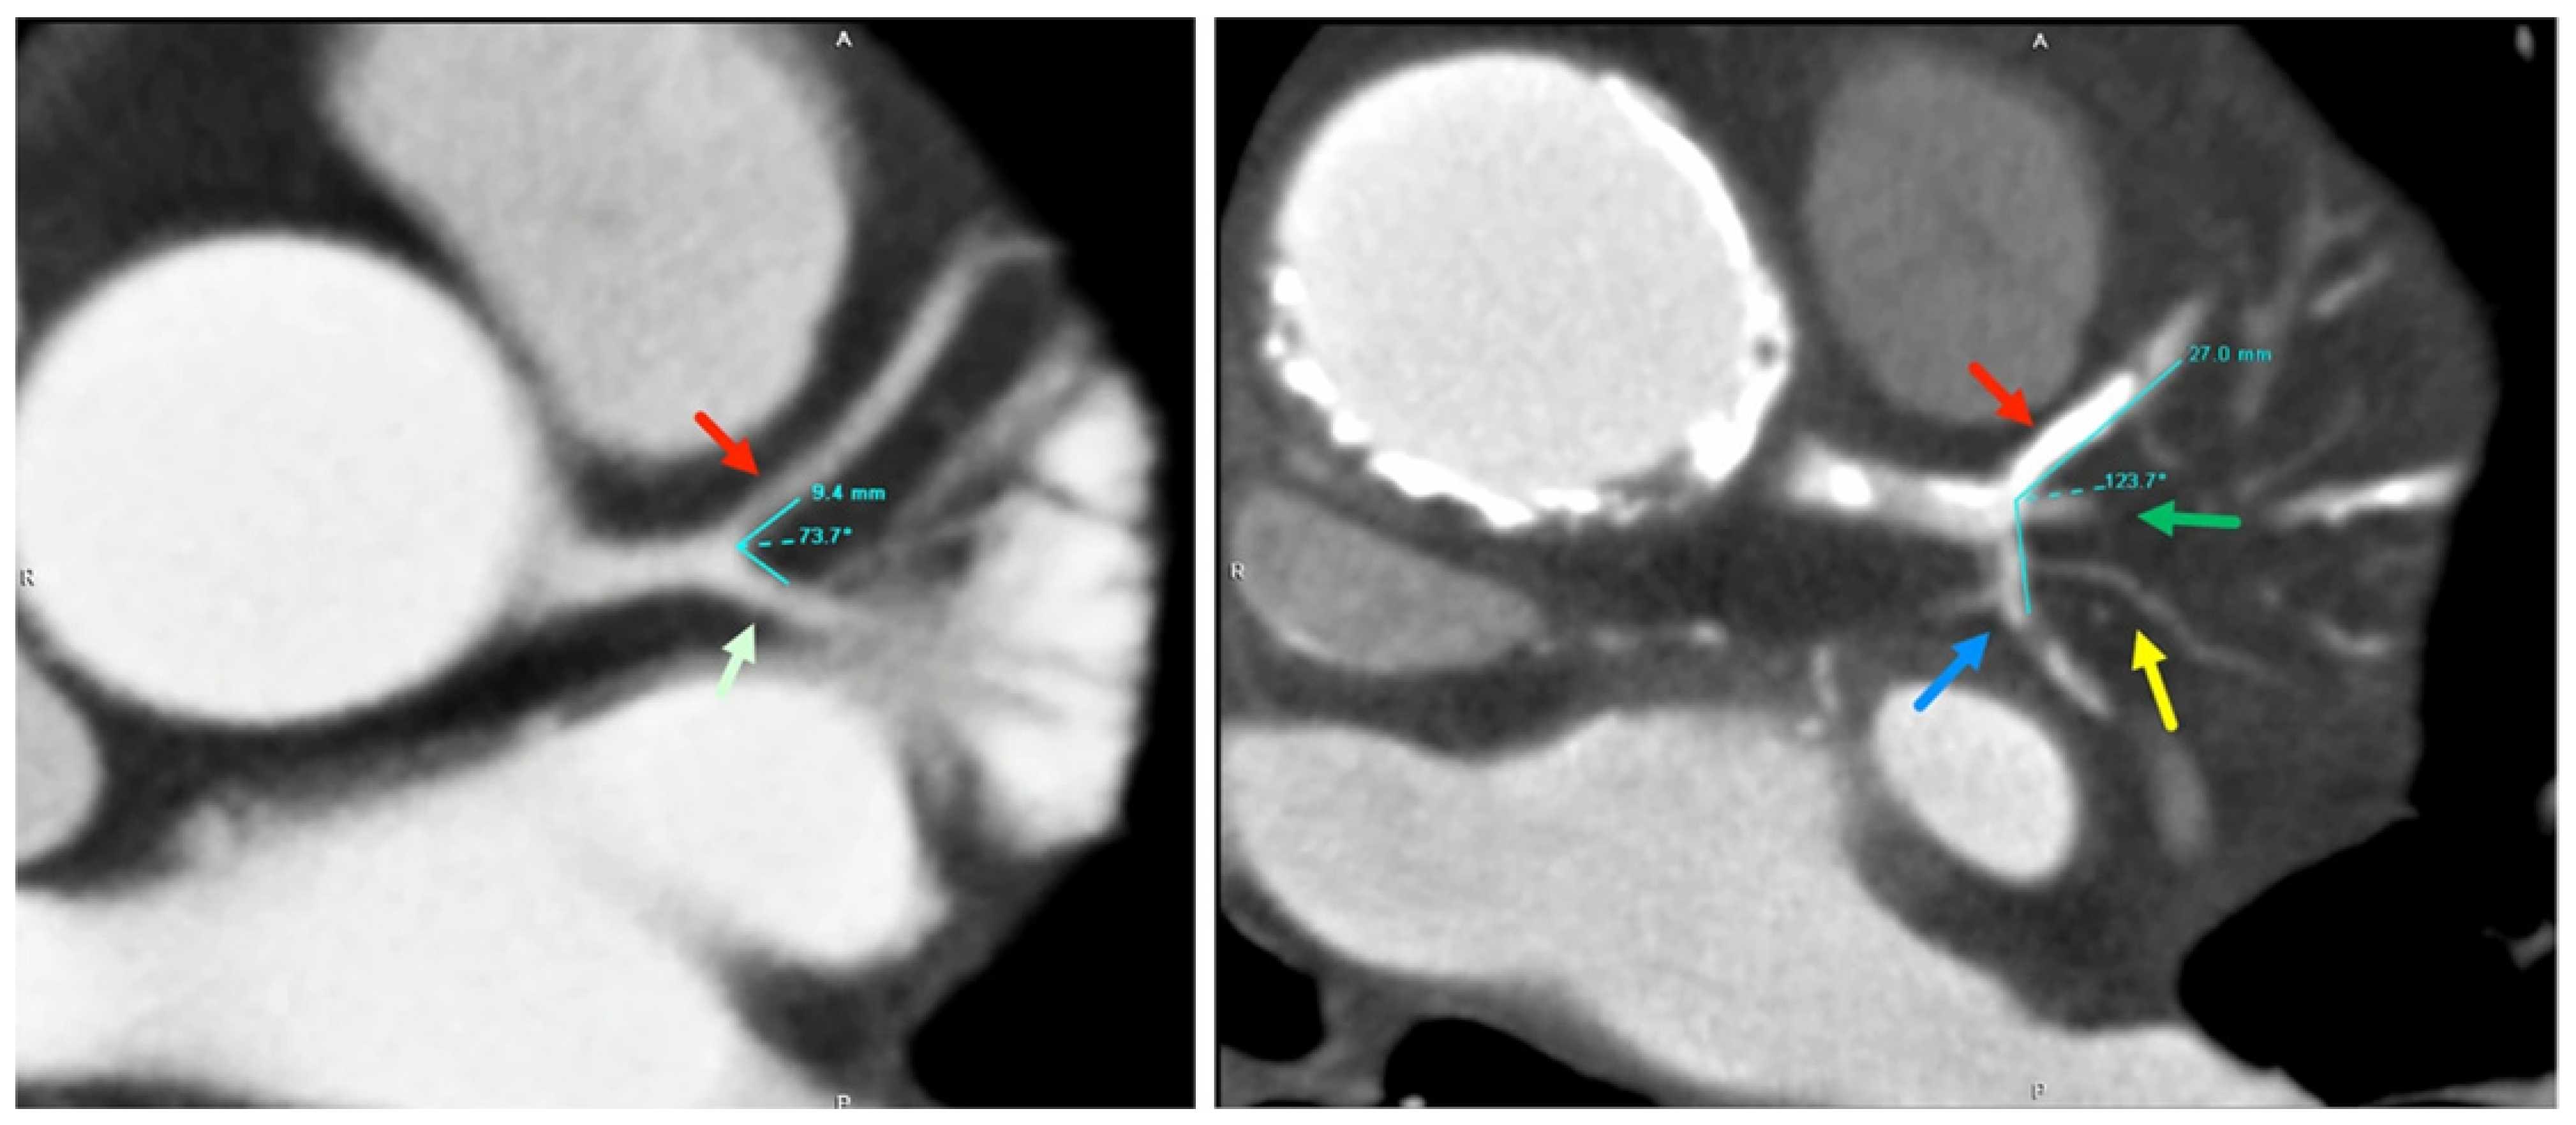

- Cui, Y.; Zeng, W.; Yu, J.; Lu, J.; Hu, Y.; Diao, N.; Liang, B.; Han, P.; Shi, H. Quantification of left coronary bifurcation angles and plaques by coronary computed tomography angiography for prediction of significant coronary stenosis: A preliminary study with dual-source CT. PLoS ONE 2017, 12, e0174352. [Google Scholar] [CrossRef]

- Sun, Z.; Xu, L.; Fan, Z. Coronary CT angiography in calcified coronary plaques: Comparison of diagnostic accuracy between bifurcation angle measurement and coronary lumen assessment for diagnosing significant coronary stenosis. Int. J. Cardiol. 2016, 203, 78–86. [Google Scholar] [CrossRef][Green Version]

- Sun, Z. Coronary CT angiography in coronary artery disease: Correlation between virtual intravascular endoscopic appearances and left bifurcation angulation and coronary plaques. BioMed Res. Int. 2013, 2013, 732059. [Google Scholar] [CrossRef] [PubMed]